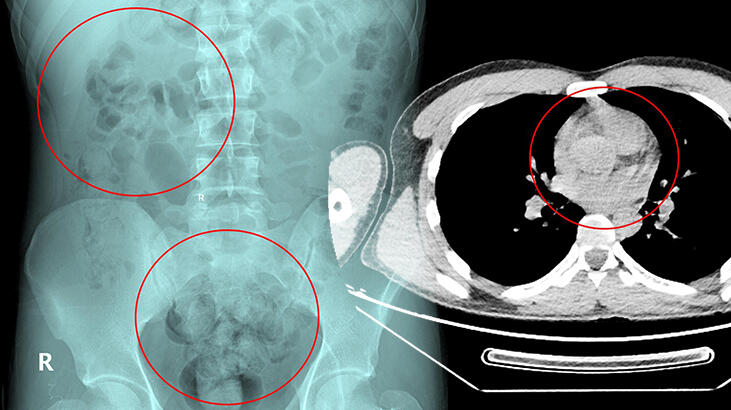

Tedavi altına alınan Narziveh’in çekilen röntgen filminde midesinde cisim tespit edildi. Ameliyata alınan Zarziveh’in midesinden 2’si patlamış 72 adet kapsül halinde uyuşturucu madde çıkarıldı. Gördükleri manzara halinde şaşkına dönen doktorlar durumu polise bildirdi.

Gelen polis ekiplerinin yaptığı incelemede 890 gram uyuşturucu maddenin metamfetamin olduğu belirlendi. Narziveh, 5 gün süren tedavisinin ardından Narkotik Mücadele Şube Müdürlüğü ekiplerince gözaltına alınarak emniyete götürüldü. 10 gün önce İstanbul’dan Van’a gittiği ve oradan da Ankara’ya geldiği saptanan şüpheli Narziveh, poliste susma hakkını kullanarak ifade vermedi. Soruşturma sürdürülüyor.